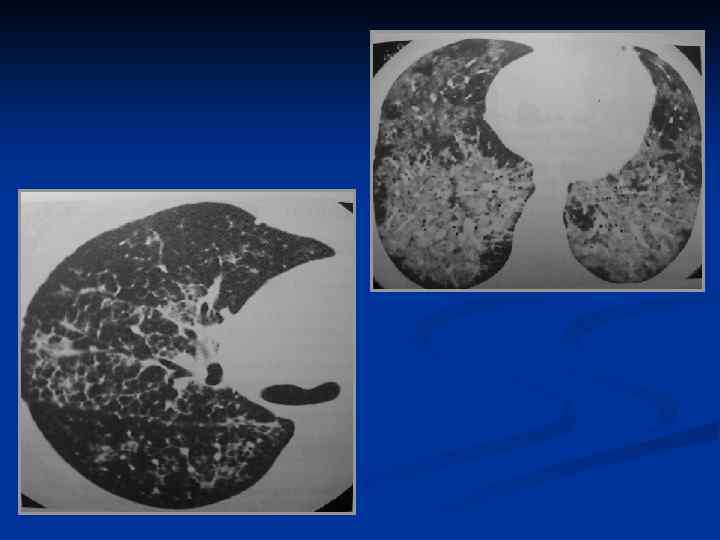

Пневмоцистная пневмония

По типу долевой, бронхопневмонии, интерстициальной ПН. • возможно диффузное двустороннее альвеолярное • или смешанное альвеолярноинтерстициальное уплотнение • м. б. множественные мелкие абсцессы: при гематогенном распространении распределяются хаотично, при аспирации – перибронхиально • миллиарно-нодулярное распределение Инвазивный кандидоз – подозревать при «ПН» негативной к стандартному лечению, либо при кандидозе ротовой полости, пищевода